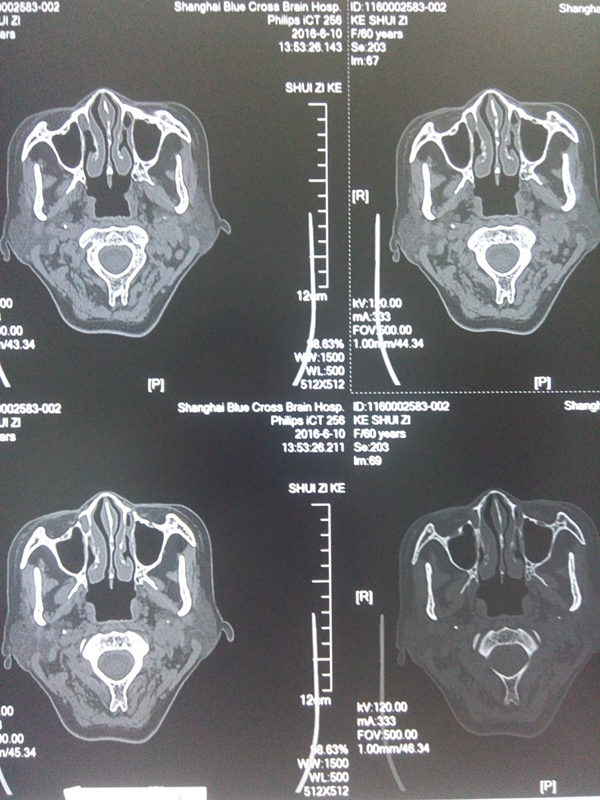

CT掃描雙側(cè)莖突無異常增生